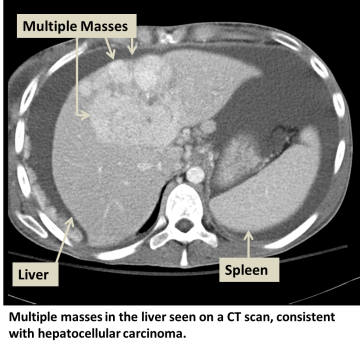

Hepatocellular carcinoma (HCC) is the most common type of primary liver cancer. Primary liver cancer refers to cancer that originates in the liver rather than cancers from other organs that metastasize to the liver (see metastatic liver cancer). HCC can start as a single tumor or as several tumor nodules across the liver.

Diagnosis and Screening

In addition to a physical examination, laboratory tests and imaging studies may be needed. These tests may also be necessary at regular intervals to detect early cancer if certain risk factors are present. Our physicians may enroll you into such a screening or surveillance program. The tests may include:

- Ultrasound

- CT scan

- MRI